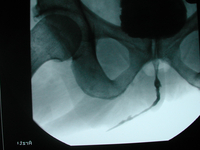

Harnröhrenchirurgie

Ursachen. So kann beispielsweise eine „harmlose” Entzündung der Harnröhre oder aber auch das „einfache” Einlegen eines […]